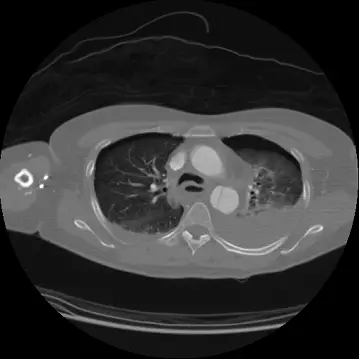

影像分析:

- 胸部 axial CT:雙肺多處挫傷、肋骨骨折;縱膈大動脈邊緣平滑,未見假性囊或媒介層剝離,亦無大量血氣胸,說明主動脈完整且胸腔失血量有限。